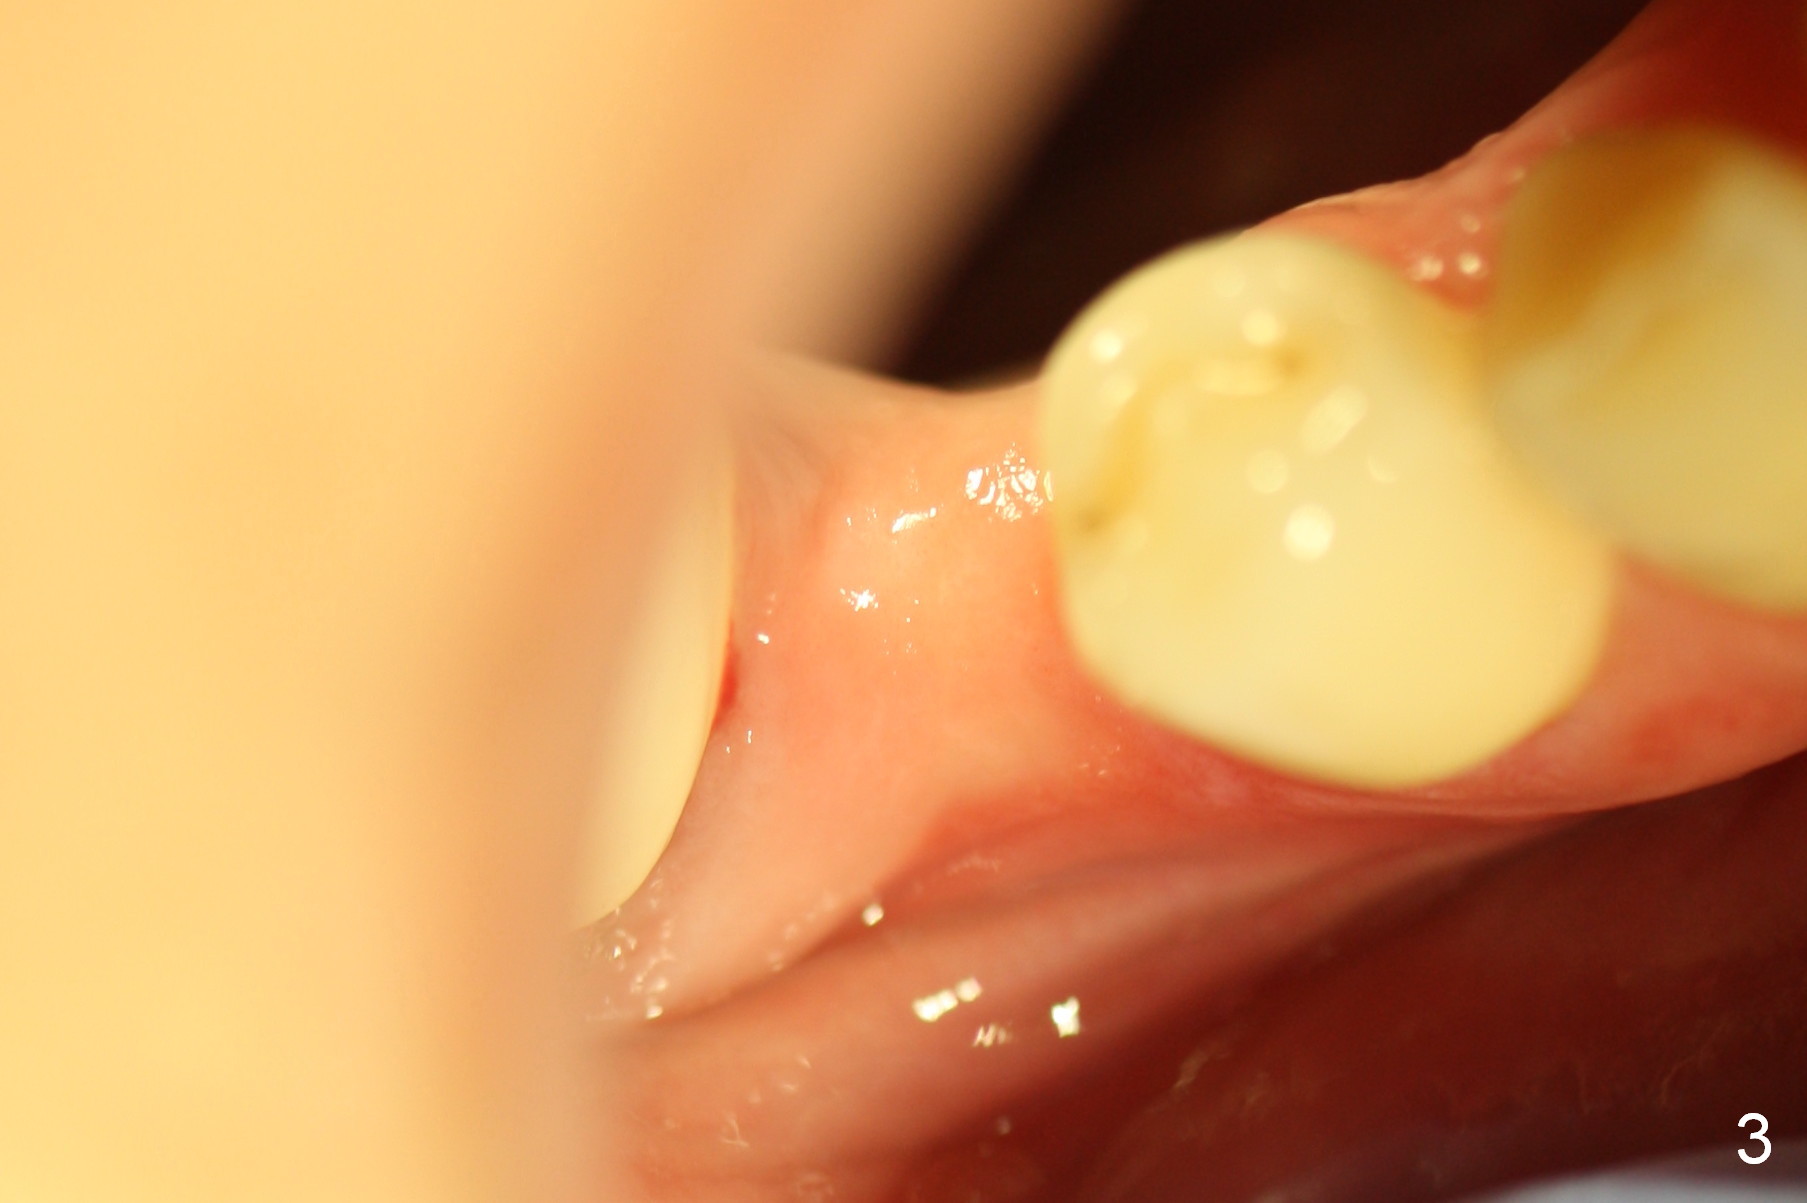

A 57-year-old woman will return for implant placement at #29, which has narrow space mesiodistally (Fig.1,2), buccolingually (Fig.3) and vertically (Fig.1, i.e., close to the Mental Loop (red outline)). Use a 2.5 or 3 mm tissue-punch from the 1-piece implant kit for access. After removal of the gingival tissue at the access, measure the tissue depth. To avoid complication associated with the narrow ridge, an incision approach appears more appropriate. The initial depth will be 12 mm using 1.2 mm drill and take PA.